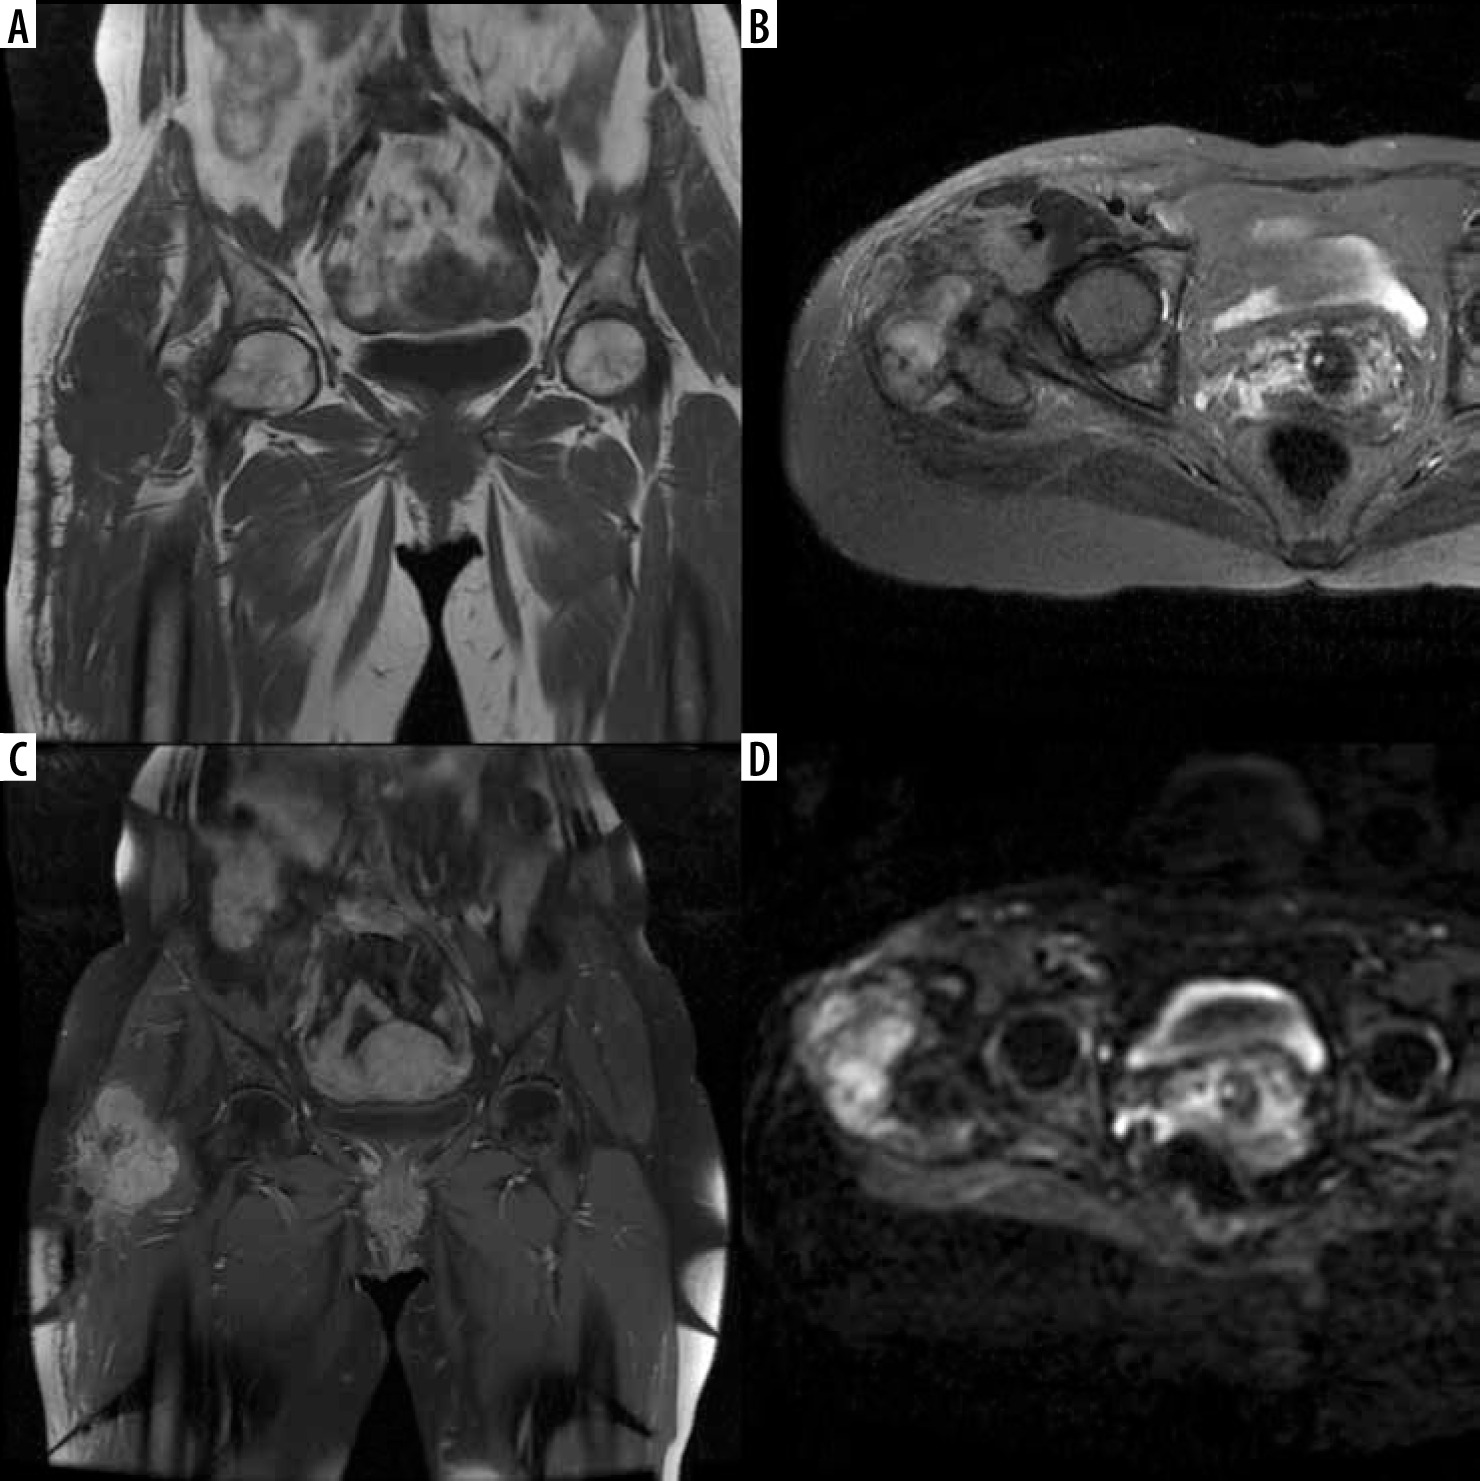

Figure 2

In month 12 magnetic resonance imaging (MRI) follow-up of a 67-year-old patient operated for a liposarcoma located in the proximal of the groin the lesions (A) hypointense in T1-weighted images, (B) hyperintense in T2-weighted images and (C) that enhanced with contrast after IV contrast administration were primarily regarded as recurrent masses and (D) were hyperintense in diffusion weighted images and the ADC value was calculated as 1.3 × 10-3 mm2/s in the apparent diffusion coefficient (ADC) map